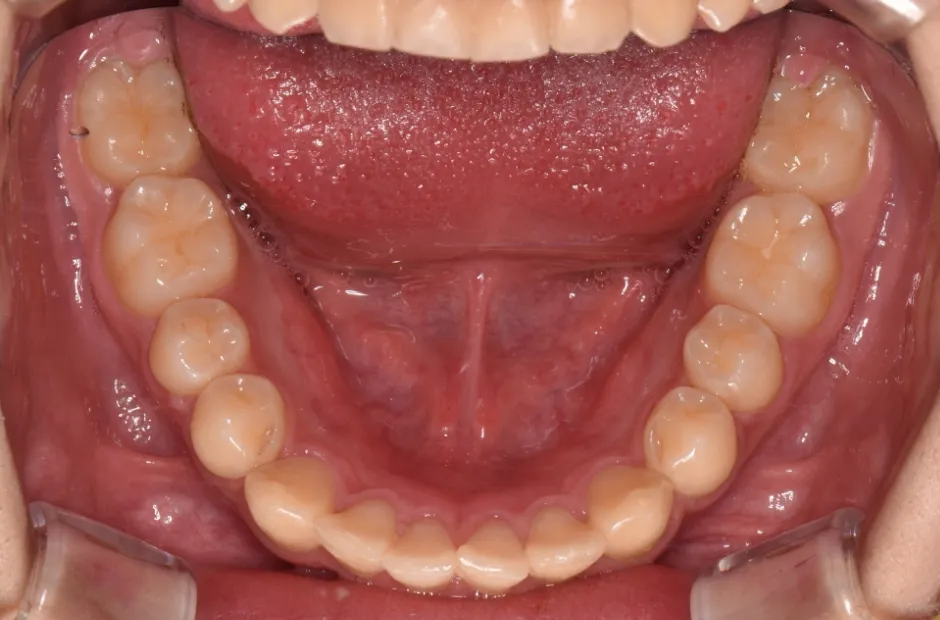

リンガルアーチ

| 診断名・主訴 | 反対咬合 |

|---|---|

| 年齢・性別 | 14歳・女性 |

| 治療期間・回数 | 2年6か月 |

| 治療に用いた主な装置 | リンガル |

| 抜歯部位 | 上顎5,5 下顎4,4 |

| 治療費 | 100万円(税抜) |

| リスク・副作用 | 装置による違和感・疼痛・歯肉退縮・歯根吸収・虫歯のリスクなど |

治療後